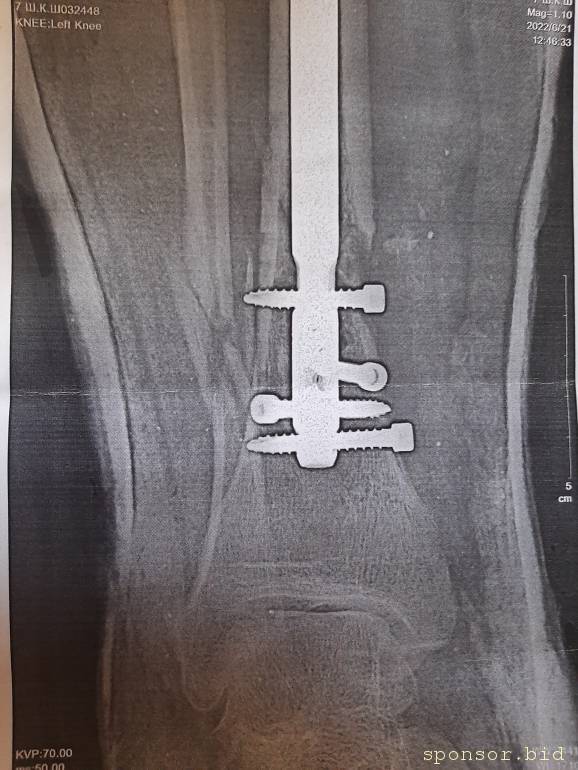

Вот что со мной произошло: летом прошлого 2022 года я неудачно упал, и сломал левую ногу, да так, что всё не закончлось просто гипсом. Перелом был сложным, пришлось делать операцию, ставить биос. Операция прошла с осложнениями, был свищ, нога после операции долго не заживала. Потом сломался крепёжный саморез, стало ещё хуже. Заболела правая нога в колене и бёдре. На приёме у врача сказали нужна операция! И в ближайшее время! Но я на больничном уже целый год, и после такого продолжительного лечения, все мои финансы на нуле. Ходить не могу, спать не могу, мучают постоянные боли. У меня развился сахарный диабет, ноги болят, появилась венозная недостаточность и варикоз. Мне всего 41 год. Получается я останусь инвалидом навсегда... Но у меня есть двое детей 5 и 14 лет... В данный момент я не могу встать на ноги из-за отсутствия финансовых средств. Моя мама Лариса Андреевна, помогает мне по мере своих сил. Ей приходится работать на производстве. Но ей уже 75 лет...

Нужна помощь сыну сотрудницы Не может ходить. - 20230719_135246.jpg